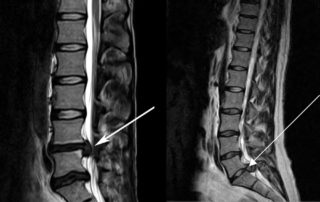

- Рентгенография визуализирует косвенные признаки остеохондроза, такие как сближение позвонков. Однако состояние межпозвоночного диска не отображается, для этого назначают КТ или МРТ. Эти методы также помогают диагностировать радикулит.

- Защемление нерва определяется с помощью электронейрограммы, МРТ и КТ. Мануальный осмотр также может быть информативным, так как компрессия может снижать рефлексы и чувствительность.

Для выявления врожденных патологий и новообразований различной этиологии проводят компьютерную и магнитно-резонансную томографию.

Для выявления различных новообразований в спинном мозге, позвоночнике и мягких тканях проводят магнитно-резонансную и компьютерную томографию.